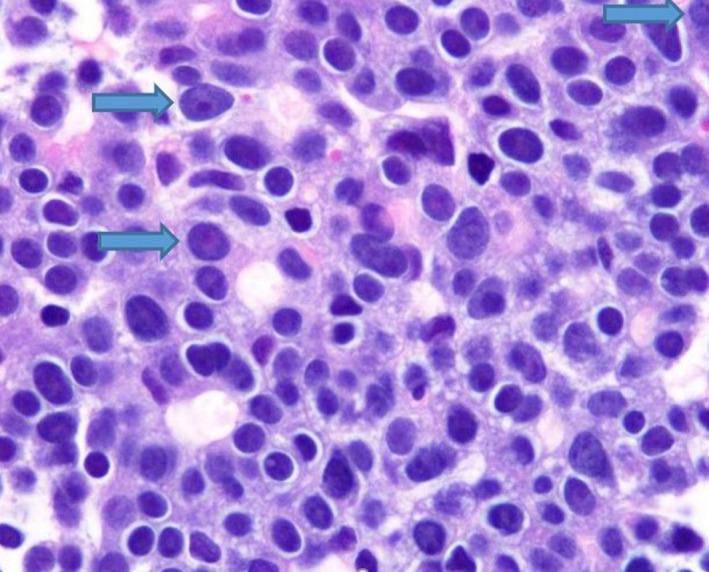

脂肪酶分泌过多综合征:晚期胰腺腺泡细胞癌的一种罕见皮肤表现。

Lipase hypersecretion syndrome: A rare cutaneous manifestation of advanced pancreatic acinar cell carcinoma.

Clin Case Rep. 2020 Mar 12;8(5):905-910. doi: 10.1002/ccr3.2785. eCollection 2020 May.